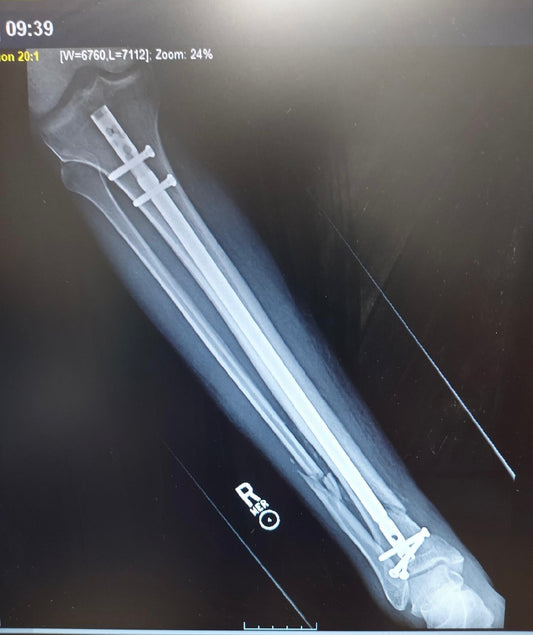

First, apologies for no updates before now... But- we have news! James is just past two months from the surgery and has been given the OK to start putting weight...